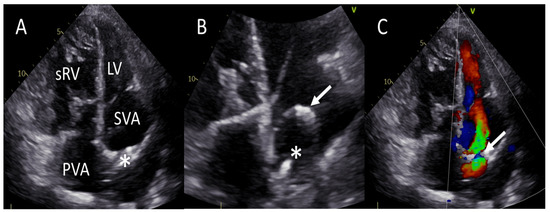

2.2. Patient B